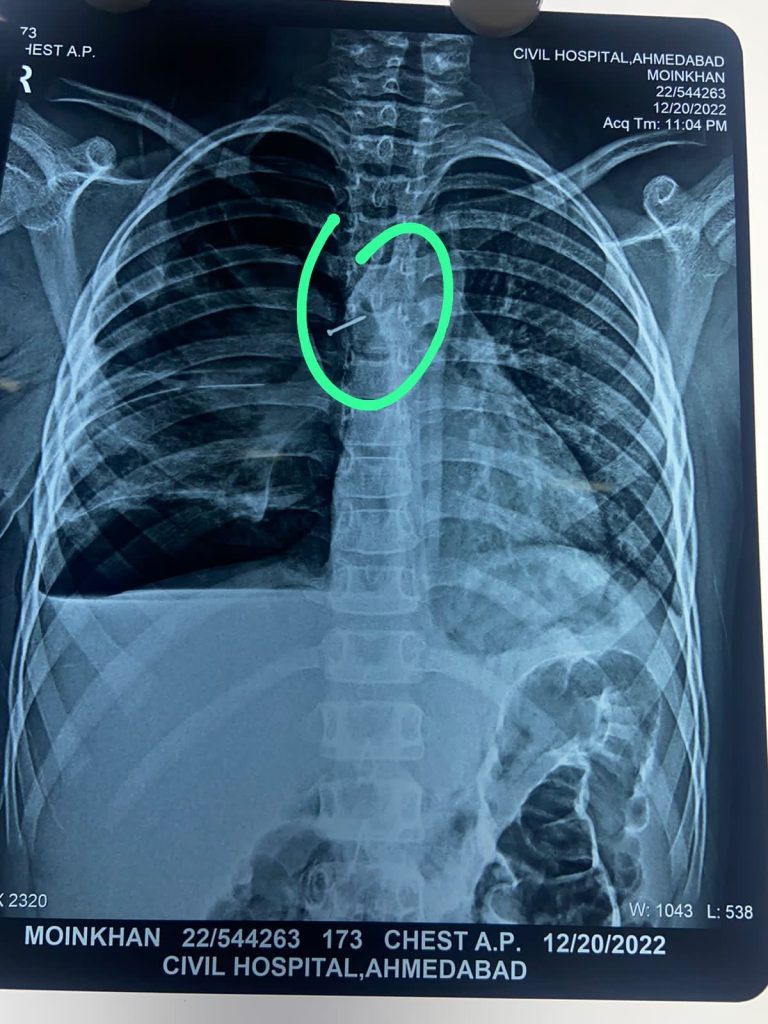

અમદાવાદ સિવિલ હોસ્પિટલના તબીબોએ બ્રોન્કોસ્કોપી કરીને બાળકની શ્વાસનળીમાંથી સોફ્ટબોર્ડ પીન સાવચેતીપૂર્ણ બહાર કાઢીને સર્જરી પાર પાડી અમદાવાદ...